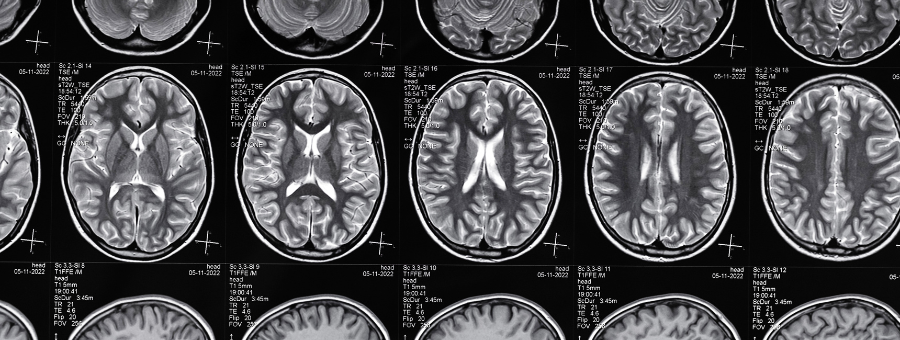

At Health Point Diagnostics, our Radiology Services deliver high-quality imaging using advanced digital technology to ensure precise diagnosis and better clinical outcomes. We are committed to offering safe, patient-friendly procedures supported by experienced radiologists and skilled technicians. With quick report turnaround and clear, detailed imaging, we make sure you and your doctor have the information needed for timely medical decisions — because accuracy matters in every scan.

At Health Point Diagnostics, we combine advanced digital imaging technology with expert interpretation to provide precise, clear, and reliable results. Our radiology department is equipped with modern, low-radiation systems that ensure patient safety without compromising image quality. Every scan is handled by trained technicians and reviewed by experienced radiologists to support fast, accurate diagnosis. With minimal wait times, a comfortable testing environment, and quick report delivery, we make your diagnostic journey smooth and stress-free.

At Health Point Diagnostics, we understand that speed, clarity, and accuracy are essential when it comes to radiology. That’s why our advanced digital imaging systems are designed to deliver high-quality scans quickly, without long wait times or unnecessary delays. Every image produced offers the clarity needed for precise diagnosis, helping doctors make informed decisions with confidence. Backed by a team of expert radiologists and modern low-radiation technology, we ensure results you can trust — because your health deserves nothing less.